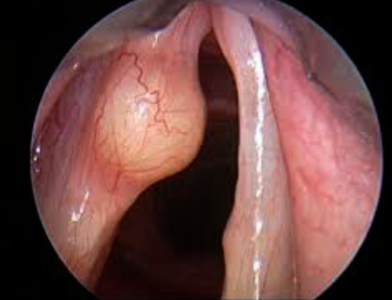

Q40: Subglottic Stenosis, Vocal Cord Cyst

-

Question: An 18 -months- old child brought to the ER with history of continuous stridor and difficulties during sleeping.

Answer:

- A- What is the diagnosis based on the telescopic picture?

- Subglottic stenosis

- B- What is the grade?

- Grade 3

Question: A 33- year-old male presented with 6 months history pf breathy voice and voice fatigue, endoscopic picture showed below.

- A- What is the diagnosis?

- vocal cord cyst

- B- What is the definitive management ?

- surgical excision